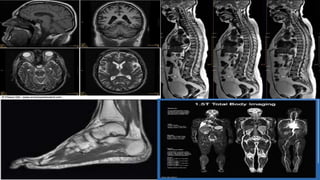

• Una resonancia magnética (RM) es un examen

imagen lógico que utiliza imanes y ondas de radio

potentes para crear imágenes del cuerpo. No se

emplea radiación (rayos X).

• Las imágenes por resonancia magnética solas se

denominan cortes y se pueden almacenar en una

computadora o imprimir en una película. Un

examen produce docenas o algunas veces cientos

de imágenes.